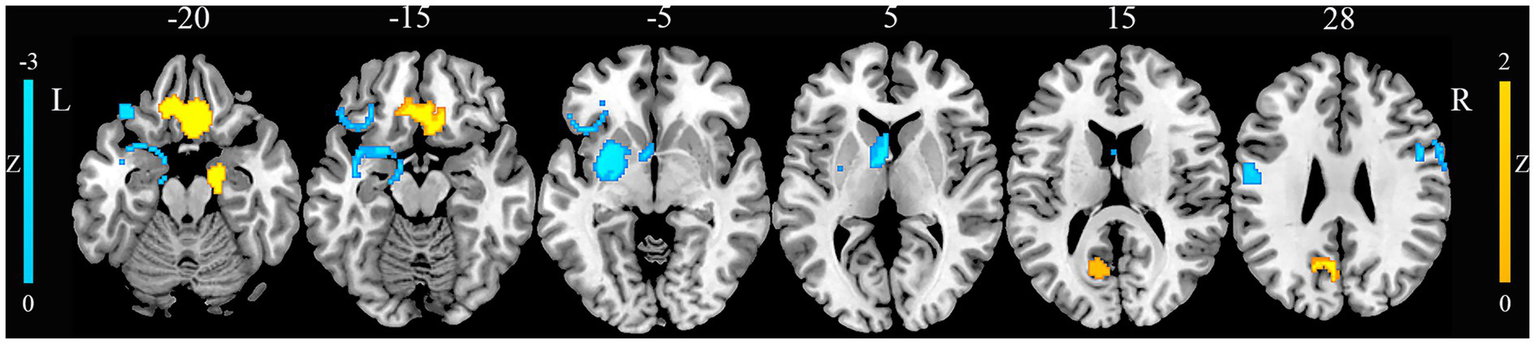

Compared with HCs, patients with JME exhibited increased GM in the right gyrus rectus, right parahippocampal gyrus, and left precuneus (Figure 2). Conversely, patients with JME showed decreased GM in the left putamen, left postcentral gyrus, right precentral gyrus, and left inferior frontal gyrus (Figure 2). The jackknife sensitivity analyses reveled that the above-mentioned regional GM alterations were highly robust in JME. The heterogeneity analysis revealed significant unexplained between-study variability of GM changes in brain regions, including the left inferior frontal gyrus and left precuneus. The funnel plots showed no obvious asymmetric of all significant brain regions. The quantitative assessment measured by Egger’s tests revealed publication bias in the right parahippocampal gyrus (Table 1).

Figure 2

Gray matter alterations in juvenile myoclonic epilepsy. This figure illustrates brain regions showing significant gray matter alterations between patients with juvenile myoclonic epilepsy and healthy controls. L, left; R, right.